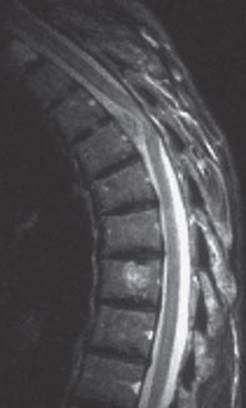

Fig. 7.4 Metastatic carcinoma of the breast. The MR image reveals destruction of several thoracic vertebral bodies and spinal cord compression by tumor projecting into the vertebral canal at a mid-thoracic level.

Fig. 7.5 Extramedullary meningioma at T4, based on the ventral dura mater. Spinal cord compression is clearly visible. (T2-weighted MR image.)